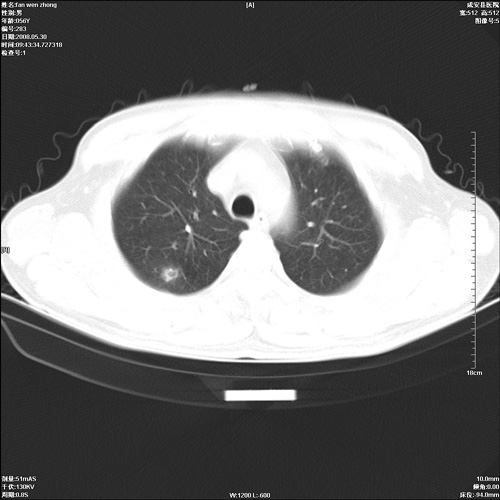

病人 男 56岁 一周前高热,体温达39-40度,经抗炎治疗后,体温渐降,达37,5-38度,轻微咳嗽,胸部不适 查白细胞为1.3万 行ct检查,请分析。

双肺内可见多发结节状病灶,并见小空洞,病人高热,白血球增高,应该是典型的迁徙性肺脓肿(多为金黄色葡萄球菌感染)。查一下口腔等其它部位有无感染灶。

双肺内可见多发结节状病灶,并见小空洞,病人高热,白血球增高,应该是典型的迁徙性肺脓肿(多为金黄色葡萄球菌感染)。建议治疗后复查.